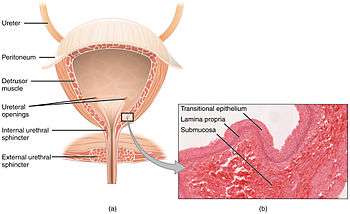

The urinary bladder is lined with transitional epithelium. It does not produce mucus.[4] The internal lining of the bladder wall is termed the urothelium and lamina propria, and this layer is thought to regulate some aspects of the overall bladder physiology in response to stimuli such as stretch during filling.[5]

Vertical section of bladder wall.

Vertical section of bladder wall.- Layers of the urinary bladder wall and cross section of the detrusor muscle.

Detrusor muscle

The detrusor muscle is a layer of the urinary bladder wall made of smooth muscle fibers arranged in spiral, longitudinal, and circular bundles. When the bladder is stretched, this signals the parasympathetic nervous system to contract the detrusor muscle. This encourages the bladder to expel urine through the urethra. A meta-analysis on the effect of voiding position on urodynamics in males found that sitting down allows for improved contraction of the detrusor muscle.[6]